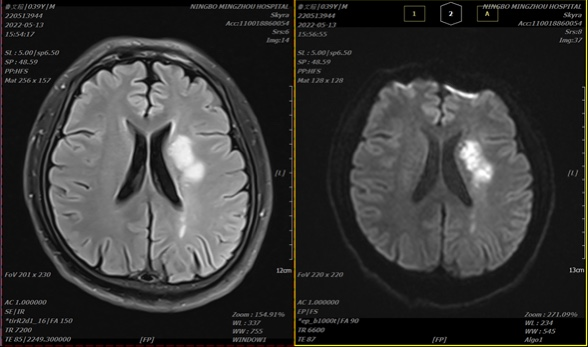

做了磁共振检查后,医生发现他左侧的大脑半球已经出现一个比较大的梗死,确诊为脑梗死、左侧颈内动脉闭塞。

由于徐先生的颈内动脉闭塞,左侧大脑半球广泛缺血严重,此时用药已于事无补,最要紧的便是打通血管、畅通血流、恢复灌注,降低再次出现脑梗死的几率。

▲术前血管闭塞,血供受阻